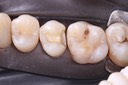

Photos of Clinical Operations

Drs. Peter Kearney, Terry McKay, John St. Germain, and Laurie Vanzella - Mentors